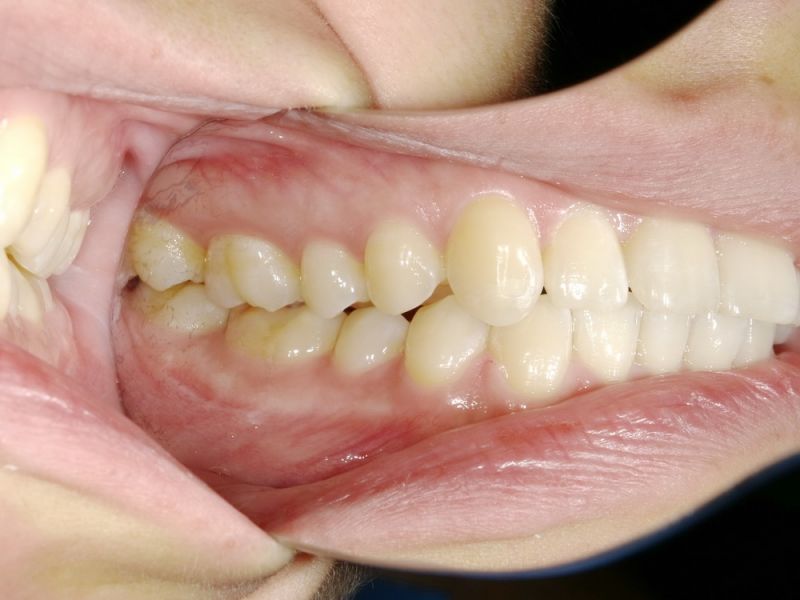

Ganz aktuell war die Patientin bei einer Hauszahnärztin, die auf die Idee kam der Patientin zwei Eckzahnfacetten im Oberkiefer zu installieren, mit dem Ergebnis, dass die Beschwerden der Patienti sich nochmals verschlechtert haben.

Es erfolgen die Maßnahmen der funktionellen Erstuntersuchung und die Herstellung und Eingliederung eines adjustierten Aufbissbehelfs zum Nachweis einer CMD.

Es erfolgen die Maßnahmen der klinisch manuellen Erstuntersuchung und nachfolgend die Maßnahmen zu Herstellung und Eingliederung eines adjustierten Aufbissbehelfs